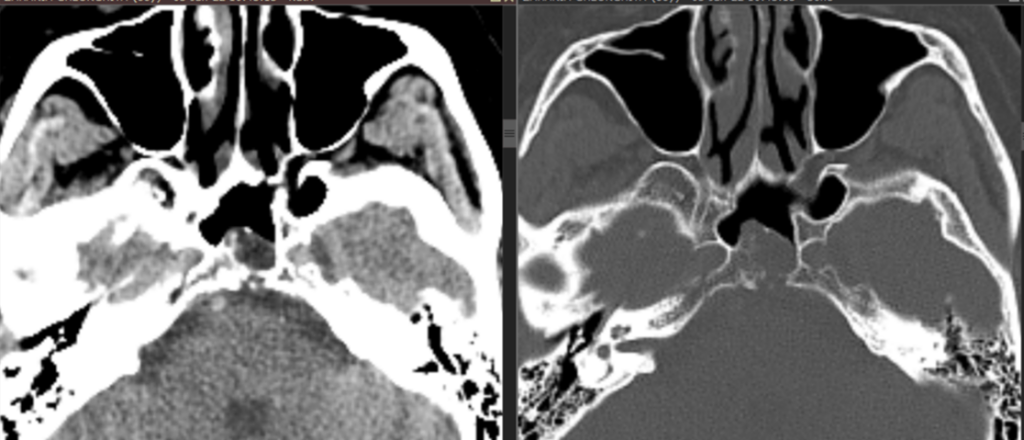

Fig 5: reconstrucţie axială din achizitie CT în fereastră de parenchim cerebral şi în fereastră de os – la examinarea CT se vizualizează optim calciul și, în acest caz, depășirea corticalei posterioare a clivusului.